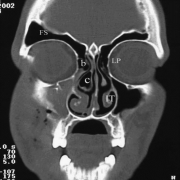

Radiographic imaging is the hallmark of frontal sinus injury diagnosis. When possible, computed tomography (CT) images should be obtained in the axial, coronal, and sagittal planes utilizing thin (1 mm) cuts. 3-D reconstructions of the entire craniofacial anatomy can also be helpful with surgical planning. Assessment of the anterior and posterior walls is best appreciated on the axial CT views and the nasofrontal duct is best seen on the coronal view; however, all images are important.

- Examination shows hypesthesia of the right forehead with mild edema of the soft tissues. Computed tomography (CT) scan shows a comminuted and depressed frontal sinus fracture that involves only the anterior wall. There is mucosal edema of the affected sinus with some evidence of aeration.

- Examination shows depression of the mid-forehead with associated minor lacerations, extensive abrasions, and edema. CT scan shows a comminuted frontal sinus fracture with involvement of both the anterior and posterior walls. There is extension into a frontoparietal skull fracture. Pneumocephalus is also noted and a CSF leak is suspected.